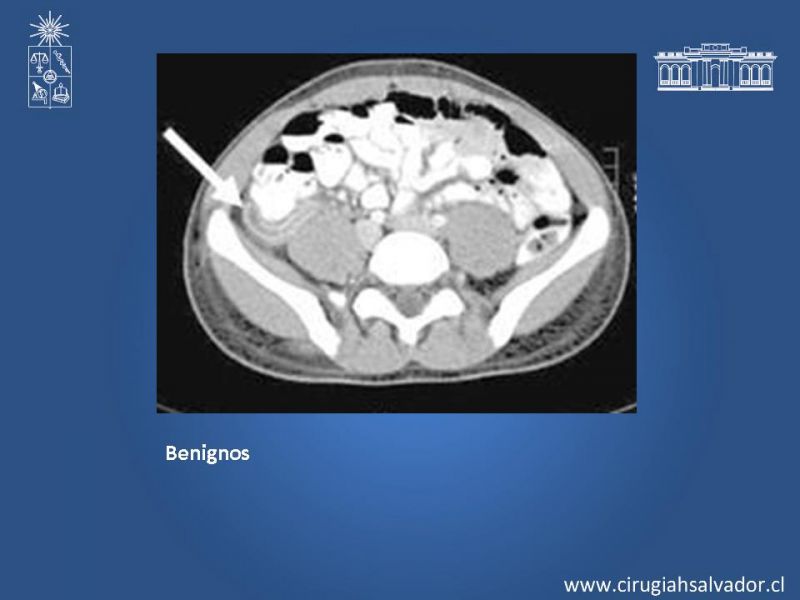

Tumor Apendicular

Coloproctología

| Autor: Dra. Jeanne Marie Chehade